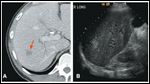

FIGURE 1

Suspicious Lesion FIGURE 2

Computed tomography (CT) scan of the abdomen and pelvis revealed a complex cystic mass in the head of the pancreas with ill-defined borders and biliary dilatation. A questionable right hepatic lobe lesion was of concern for metastatic disease (Figures 1A and 2). A right upper quadrant ultrasound demonstrated a 3.5 × 1.8 × 2.5 cm cystic mass in the pancreatic head, and a right liver lobe lesion measuring 1.7 cm (Figure 1B).